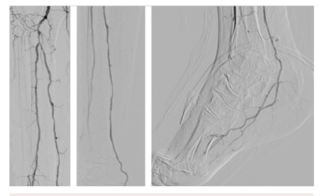

With the evolution of endovascular techniques, historically untreated patients now have options. The tibio-pedal artery minimally invasive approach is safe and feasible when patients are at risk of transfemoral access complications.